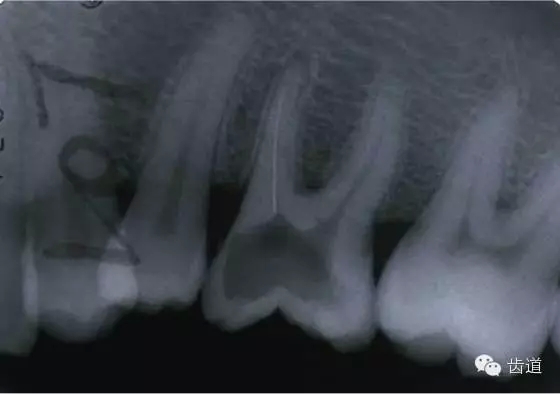

左上5牙頸部側(cè)穿

開髓時(shí)鉆針進(jìn)入方向與根管走行方向不一致,鉆針需改變方向時(shí)。

牙長(zhǎng)軸傾斜,在傾斜方向的髓腔壁易穿孔

左下6底穿

左上6底穿

根管壁穿孔多在根管彎曲處。